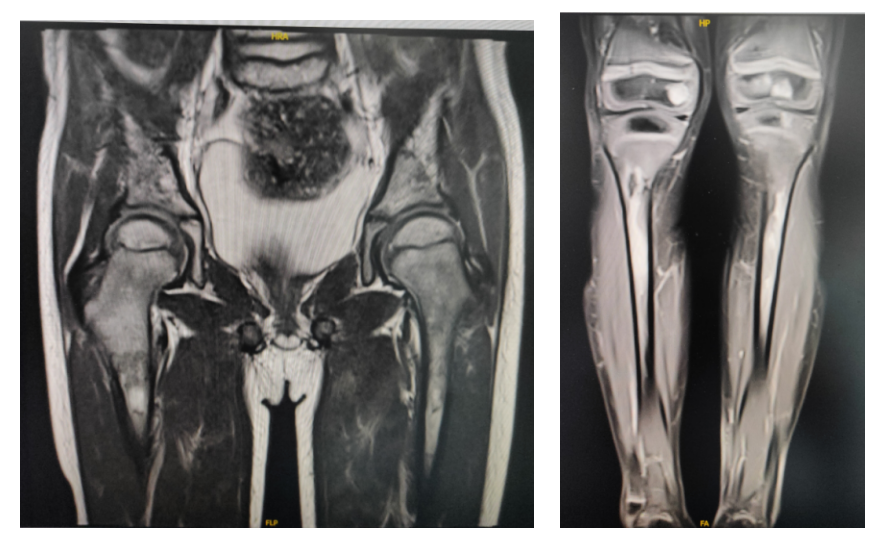

2023-5-9外院MR示:双侧髂骨、骶骨、耻骨、股骨、胫骨、腓骨、所及腰椎多发病灶,结合病史,符合骨转移及骨髓浸润,范围较前增大;双侧股骨中下段、胫骨上段骨膜反应较前增多,周围软组织明显水肿,请结合临床。

2023-5复查MR提示多发骨质破坏